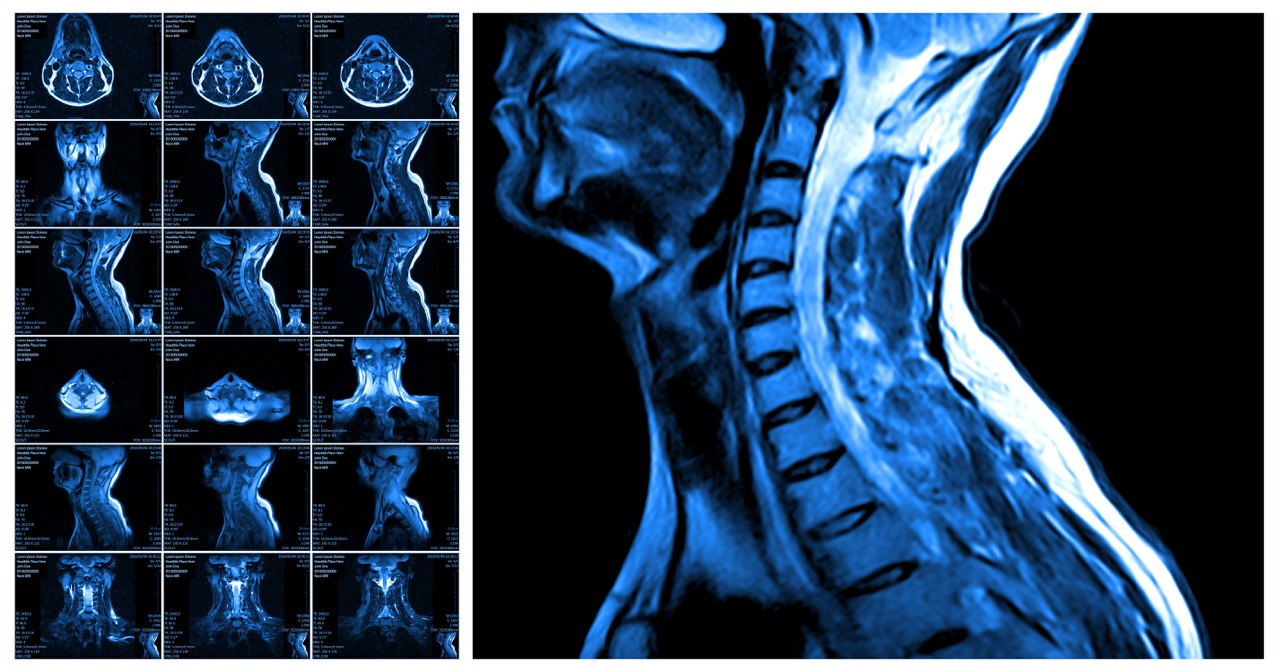

An MRI, or Magnetic Resonance Imaging, is a safe and noninvasive procedure that uses powerful magnets and radio waves to produce detailed images of your body’s internal structures. It allows doctors to detect abnormalities that might not appear on traditional X-rays or CT scans. The procedure is painless and usually takes between 20 and 60 minutes, depending on the part of the body being scanned.

During the MRI, you will lie on a comfortable table that slowly moves into the MRI machine’s tunnel. In some cases, a contrast agent like gadolinium is injected to enhance the images and highlight specific areas. For patients who feel anxious or have claustrophobia, mild sedation may be offered to help them stay calm throughout the scan. Throughout the process, the medical team will explain each step clearly and ensure you feel safe and supported.